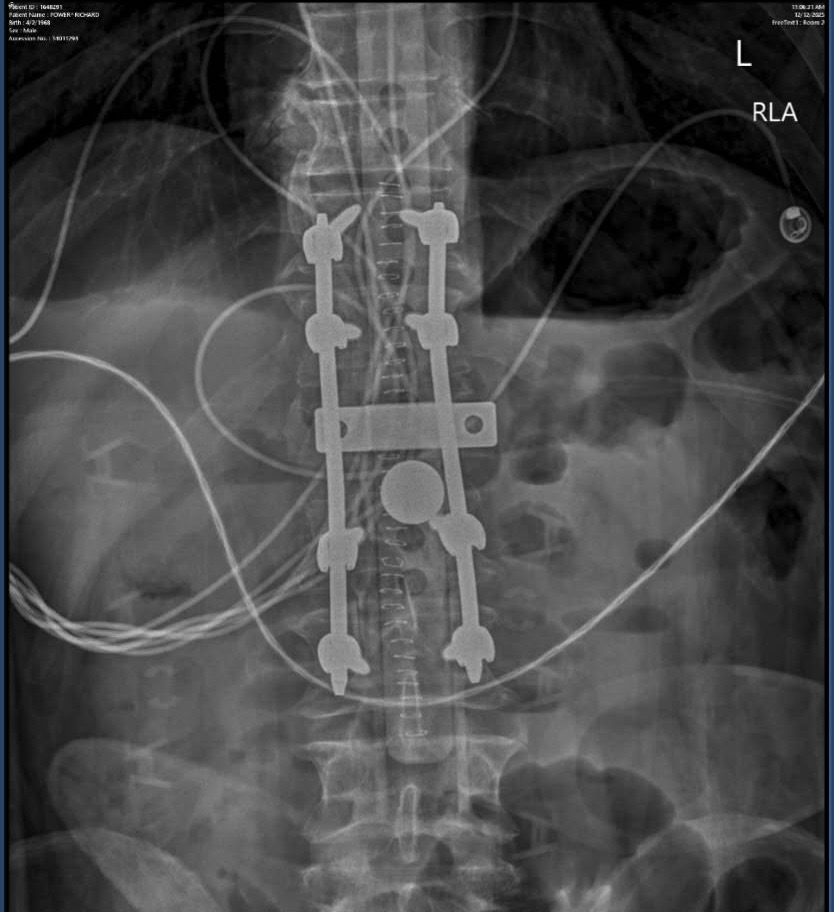

Hi everyone! I have a really good friend from work, Tina, who I’ve know for several years now. She is amazing and is always there to help and support everyone else! She is going through a tough time currently as her husband, Richard, had a work accident at the beginning of December. He was working at his construction job when a finished wall fell on top of him, landing on his head/ neck. Breaking his T12 and L1 vertebrae in his spine, as well as two other severe fractures.

He was in the hospital for 9 days and had two different surgeries during that time. Since then he has had 3 different emergency room visits and 5 doctors appointments, with 4 more coming up within the next week or so.